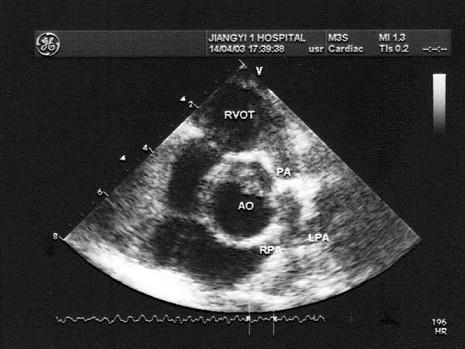

患儿青紫,存室间隔缺损,如图所示,诊断最可能?(?)A.肺动脉瓣狭窄B.主动脉内径增宽C.法洛四联症D.法洛三联症E.房间隔缺损

问题 患儿青紫,存室间隔缺损,如图所示,诊断最可能?(?)

选项 A.肺动脉瓣狭窄 B.主动脉内径增宽 C.法洛四联症 D.法洛三联症 E.房间隔缺损

答案 C